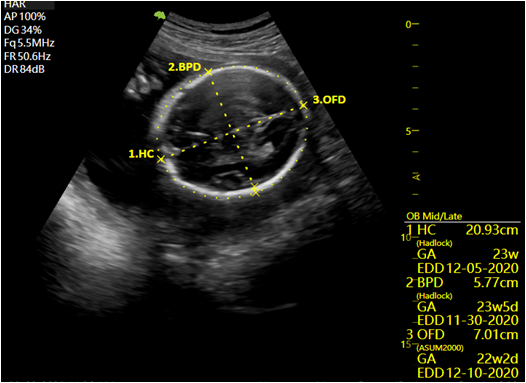

- VAim OB: KI-gestützte Vermessung der fetalen Biometric